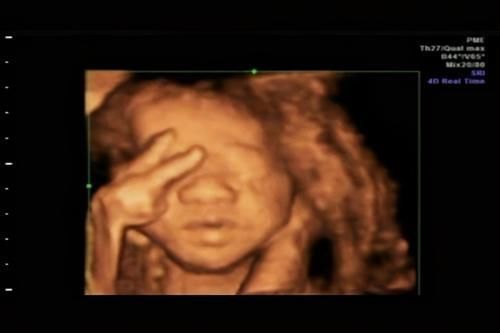

4、主要目的是为了排畸

四维彩超的目的可不是为了拍出多么好看的照片,而是通过清晰的图像去观察宝宝各方面的发育是否存在畸形。

【 宝宝|被宝宝的四维彩超照丑哭了?不是医生技术不好,而是有客观原因的】医生为了判断地更准确,会从各个角度去观察,难免有时候会出现拍照的“蜜汁角度”,看起来就比较难看了。

毕竟一个再好看的人,你从下巴这里往上照,也很难拍得好看。